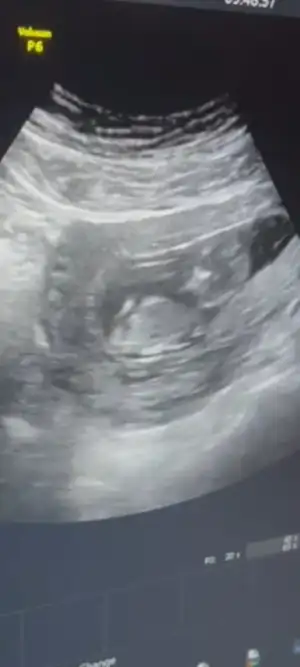

Benim de geç döllenmeydi canım sabır et biraz bende çok sabirsizlanmistim ya biraz zaman alan surecmis bende yeni öğrendim ilk bebek olduğu içinEvet gördüm .benimkide geç döllenme olduğu için eğer öyle değilse bile şuan çok küçük 4 haftamdayim